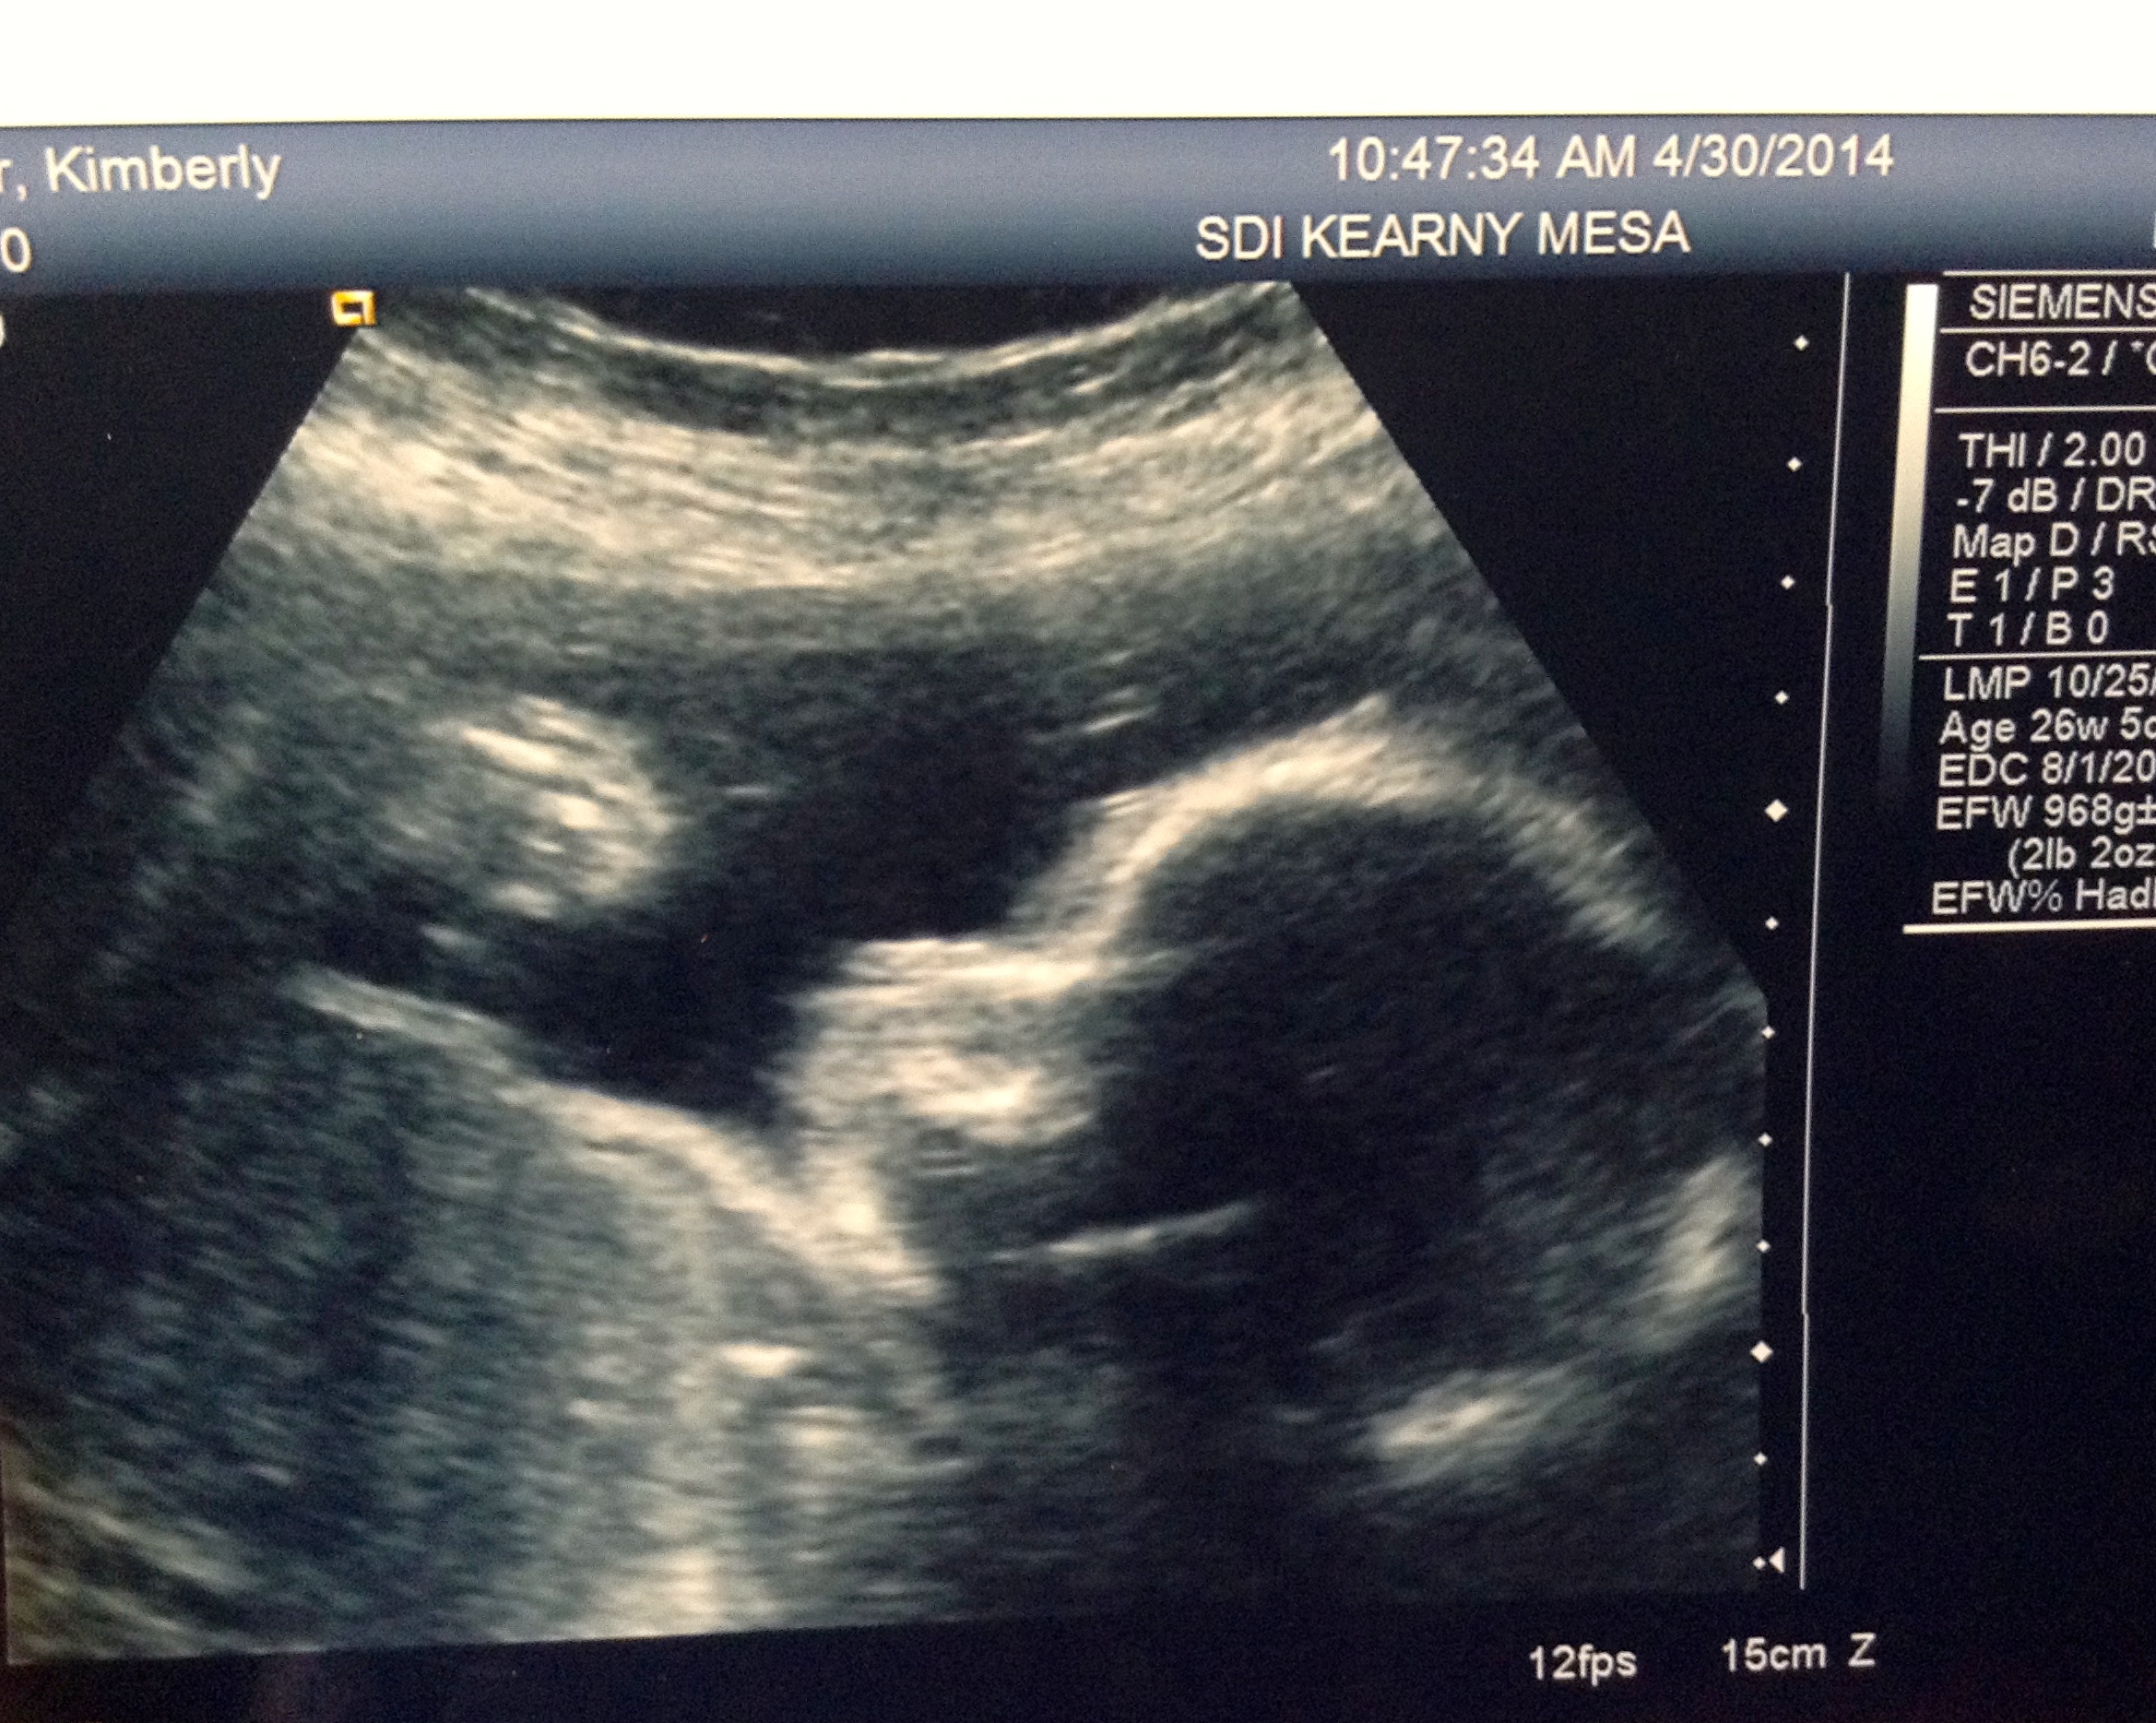

I had my ultrasound to check on the previa and my stupid placenta hasn’t moved. So I carry on as is until my next Dr. appointment until I am told what happens next. Does this change the c-section date? Will I have another ultrasound? I guess we will find out in a couple weeks.

Baby A looks good. She is head down and weighing about 2 lbs. 2 0z.